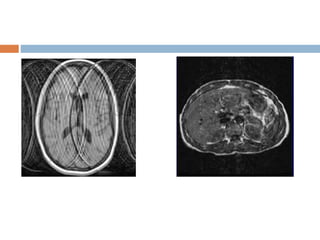

Moire fringes

 An interference pattern most commonly when

doing gradient echo images.

 One cause is aliasing of one side of the body to

the other results in superimposition.

 Can also be caused by receiver picking up a

stimulated echo.

 Similar to the effect of looking through two

window screens.

 Solution

 Improve shimming

Moire fringes  Aninterference pattern most commonly when doing gradient echo images.  One cause is aliasing of one side of the body to the other results in superimposition.  Can also be caused by receiver picking up a stimulated echo.  Similar to the effect of looking through two window screens.

Magnetic suscepbility artifact

 Distortion in the MR image especially seen in

while imaging with metallic orthopedic hardware

or dental work.

 Magnetic field inhomogenetics introduced by the

metallic object in to homogeneous magnetic

field.

 Greater at high magnetic field strength.

 Worst with long TE and gradient echo

sequences.

 Appearance

Bright and dark areas

Larger receiver bandwidth

Gradient echo and echo planar sequences

should be avoided.

The use of echo spin particularly fast spin

echo sequences should be considered.

Magnetic suscepbility artifact Distortion in the MR image especially seen in while imaging with metallic orthopedic hardware or dental work.  Magnetic field inhomogenetics introduced by the metallic object in to homogeneous magnetic field.  Greater at high magnetic field strength.  Worst with long TE and gradient echo sequences.

 Appearance Bright anddark areas  Solution Larger receiver bandwidth Gradient echo and echo planar sequences should be avoided. The use of echo spin particularly fast spin echo sequences should be considered.